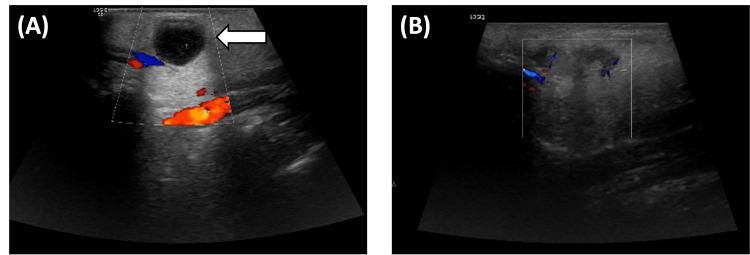

Pediatric-type follicular lymphoma (PTFL) is an extremely rare B-cell lymphoma that primarily affects children and young adults, typically in individuals under 25 years old, with a median age of 15 years. Here, we report a rare case of PTFL in a 27-year-old adult male who presented with a slow-growing mass near his left ear. Initial CT scans of the neck revealed two oval-shaped, smooth, well-defined, homogeneously enhancing soft tissue density lesions in the superficial lobe of the left parotid gland. A complete surgical excision was performed, and a postoperative ultrasound of the neck confirmed complete removal, with only hypoechoic changes observed in the parotid gland. Comprehensive immunohistochemical analysis showed CD20-positive B cells co-expressing germinal center markers CD10 and BCL6 but negative for BCL2 and cyclin D1. The Ki-67 proliferation index was notably elevated, indicating high cellular activity. Additional findings included MEF2B positivity, confirming the lymphoma diagnosis, and an immunoglobulin gene rearrangement, which demonstrated a monoclonal B-cell population consistent with a neoplastic process. CD21 staining further revealed distorted follicular dendritic cell networks and attenuated IgD-positive mantle. Fluorescence in situ hybridization (FISH) analysis showed no rearrangements in BCL2, IRF4, or BCL6, and any deletion in the 1p36 region (TNFRSF14 gene), ruling out other lymphoma types. Histologically, the nodules showed distorted secondary follicles with obscured germinal centers, confirming PTFL. At the three-month follow-up, the patient demonstrated satisfactory healing with no signs of recurrence. This case underscores the importance for oncologists to perform a thorough differential diagnosis of head and neck masses, as PTFL can present with characteristics similar to classical follicular lymphoma, IRF4-rearranged large B-cell lymphoma, pediatric nodal marginal zone lymphoma, and reactive follicular hyperplasia. A comprehensive diagnostic approach, including clinical, pathological, and immunohistochemical analyses, is essential for developing an accurate diagnosis and management plan for PTFL, especially in atypical adult presentations.

儿童型滤泡性淋巴瘤(PTFL)是一种极其罕见的B细胞淋巴瘤,主要影响儿童和年轻成人,通常为25岁以下个体,中位年龄为15岁。在此,我们报告一例罕见的PTFL病例,患者为一名27岁成年男性,左耳附近出现缓慢生长的肿块。颈部初始CT扫描显示左腮腺浅叶有两个椭圆形、边界光滑、清晰、均匀强化的软组织密度病变。进行了完整的手术切除,术后颈部超声证实已完全切除,仅腮腺出现低回声改变。综合免疫组化分析显示CD20阳性B细胞共表达生发中心标志物CD10和BCL6,但BCL2和细胞周期蛋白D1为阴性。Ki-67增殖指数显著升高,表明细胞活性高。其他发现包括MEF2B阳性,证实了淋巴瘤诊断,以及免疫球蛋白基因重排,显示与肿瘤过程一致的单克隆B细胞群体。CD21染色进一步显示滤泡树突状细胞网络扭曲和IgD阳性套区变薄。荧光原位杂交(FISH)分析显示BCL2、IRF4或BCL6无重排,1p36区域(TNFRSF14基因)无任何缺失,排除了其他淋巴瘤类型。组织学上,结节显示次级滤泡扭曲,生发中心模糊,确诊为PTFL。在三个月的随访中,患者愈合情况良好,无复发迹象。该病例强调了肿瘤学家对头颈部肿块进行全面鉴别诊断的重要性,因为PTFL可能表现出与经典滤泡性淋巴瘤、IRF4重排的大B细胞淋巴瘤、儿童淋巴结边缘区淋巴瘤和反应性滤泡增生相似的特征。对于PTFL,尤其是非典型成人病例,包括临床、病理和免疫组化分析在内的综合诊断方法对于制定准确的诊断和管理计划至关重要。